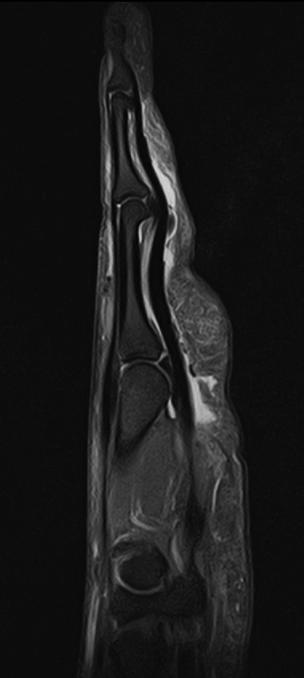

1

Finger scanned with 16ch Flex SPEEDER coil

- Sagital PD with FatSat

- Resolution: 0.6 x 0.6 mm

- Slice Thickness: 2.5 mm

“Thanks to new possibilities in scan environment and new coils the general image quality is better than before using approximately the same scan time. While overall image quality is excellent, the Knee/Foot SPEEDER coil gave us best improvement in image quality compared to the old system. Foot, ankle and knee images are excellent”, said Tommi Jauhiainen. With the new software we were also able to start abdominal scans. Water Fat Separation (Dixon, WFS) helps when fat saturation is for some reason difficult”, he concluded. //